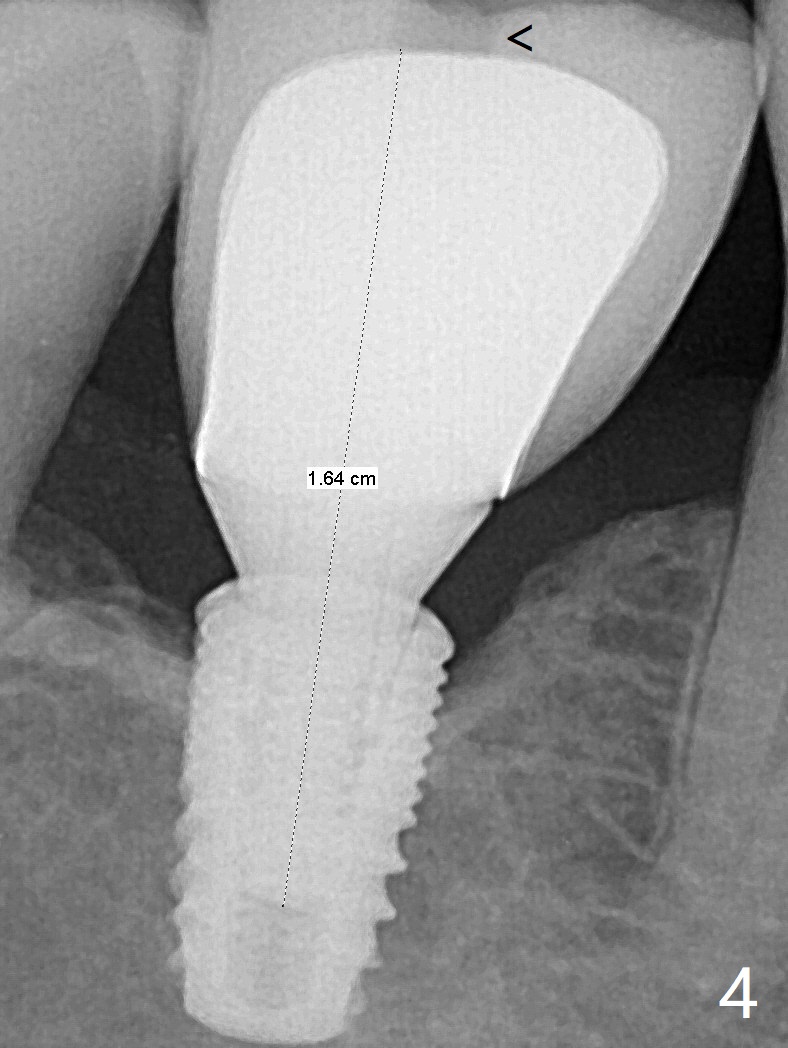

与植体(fixture)接触的基台有两部分:六角形(hex)和锥体(conical)。Hex磨损无关大局。基台穿龈部分与所谓锥体(conical)表面质地(处理)以及锥度都不一样。